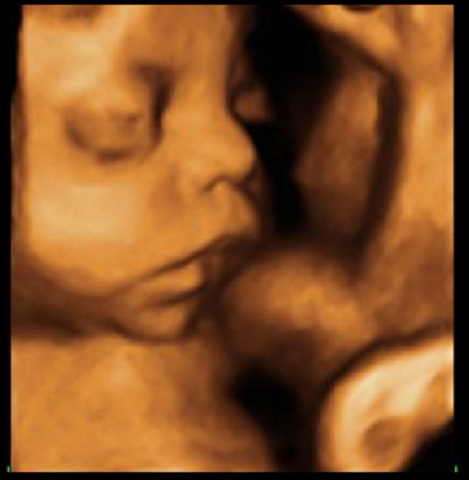

En la semana 14 de embarazo, las orejas del feto se encuentran implantadas a ambos lados de la cabeza y también los ojos se han acercado; es decir, el bebé tiene ya una carita casi perfecta, tanto que ya se distingue el puente de la nariz. Incluso se puede ver que hace algunos pequeños gestos. Además, el cuello se ha alargado y el mentón ya no descansa sobre el pecho. Ya no parece que esté enroscado.